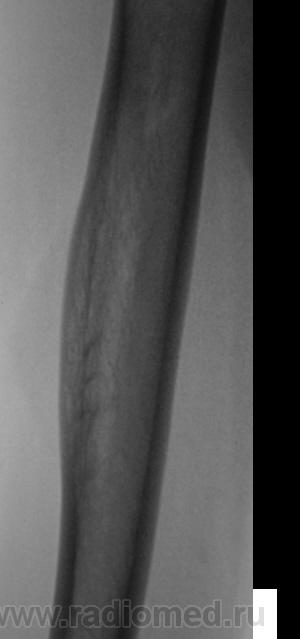

Изображения в боковой проекции с увеличением.

А что это за поперечные линии - костной перестройки, что ли?

На снимках справа латерально вроде как прослеживается "мягкотканный компонент". На левой такого нет. А может просто справа мышцы плотнее и накладываются друг на друга, т.к правша?

Мне кажется, есть локальная слоистость кортикального слоя. Надо бы спросить ту, имя которой я поклялся не упоминать.